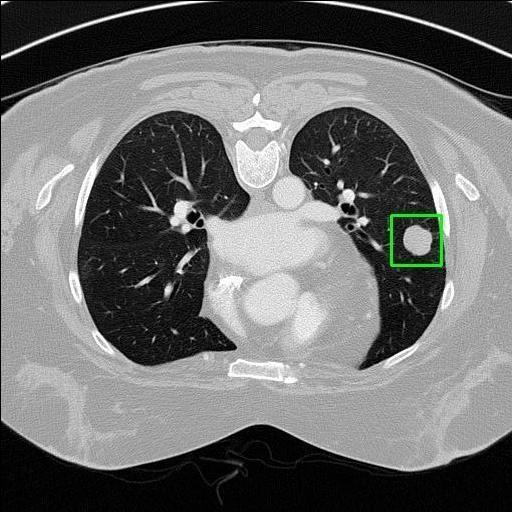

We developed an AI-based system using deep learning models for analyzing lung CT scans to detect and classify pulmonary nodules. We chose the YOLOv11 architecture for its enhanced object detection capability and adapted it specifically for medical imaging, incorporating pixel-level precision and severity classification.

Key Features: Real-time detection of nodules.

Classification into three severity levels with colored bounding boxes.

Maintaining performance on small, complex features like micro-nodules tested the limits of traditional object detectors.